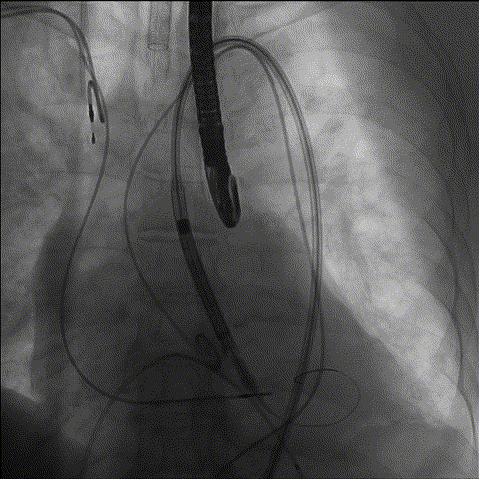

1、冠脉造影

2、主动脉根部造影